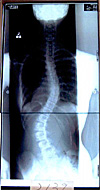

(a)長野県内大学

病院装具です。

愛知県と同タイプ |

(b)装着姿後方では腰椎は押しているが胸椎はない |

(c)装具なし

レントゲン 37度—27度 |

(d)同病院の

装具着用 42度—16度 |

(e)大塚整体指導 装具着用 8度—3度 |

《(d)(e)の装着度数の差が歴然、これが医学的立証》 |